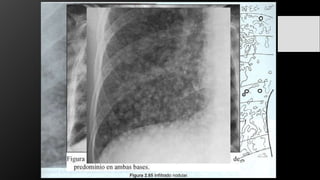

Infiltrados Pulmonares:

• Grupo de opacidades que aparecen donde normalmente existía transparencia

pulmonar. Son imágenes radiopacas que aparecen donde normalmente había imágenes

radiolúcidas.

• Los que comprometen el espacio aéreo, que son los infiltrados de tipo alveolar.

• Los que comprometen el intersticio que son los infiltrados intersticiales.

Infiltrado retículo-nodular

Conceptos Preliminares Infiltrados Pulmonares: •Grupo de opacidades que aparecen donde normalmente existía transparencia pulmonar. Son imágenes radiopacas que aparecen donde normalmente había imágenes radiolúcidas. • Los que comprometen el espacio aéreo, que son los infiltrados de tipo alveolar. • Los que comprometen el intersticio que son los infiltrados intersticiales.